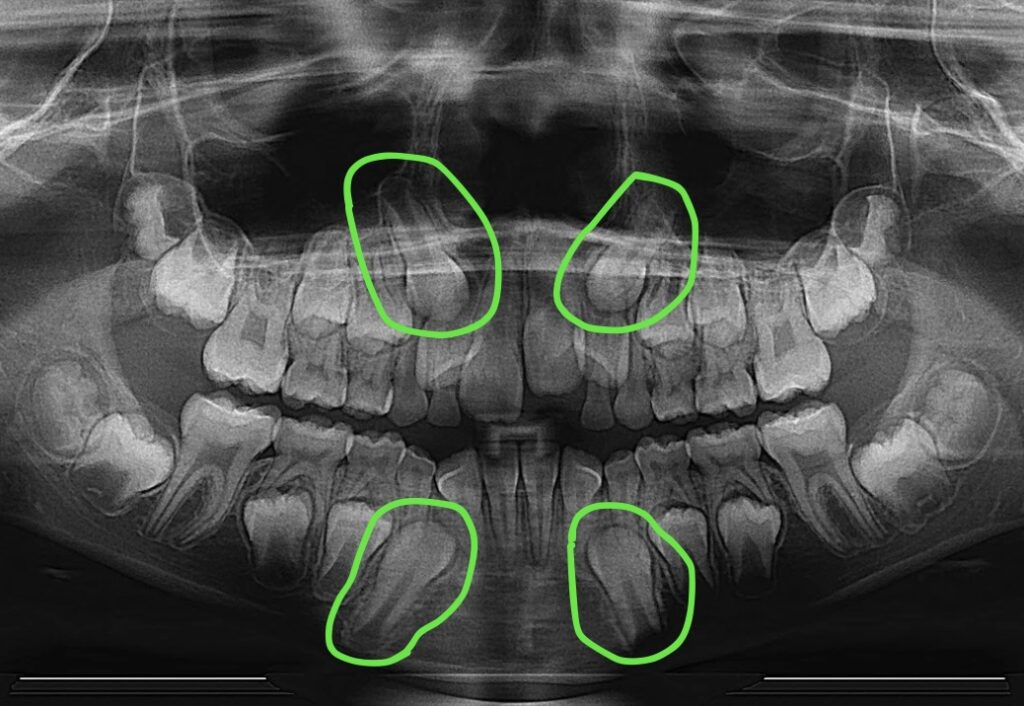

Patient. Lauren came to us a few years ago with the primary concern of "crowding." Upon taking an x-ray, we noticed all four of her canine teeth – which had not yet erupted – were positioned in such a way that they would likely harm her adjacent adult teeth. That’s not what we want! Thanks to the x-ray shown below, we knew that we needed to prepare Lauren’s mouth for the eventual eruption of those teeth!